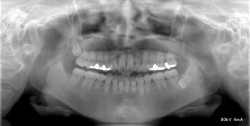

レントゲン デジタル式パノラマX線診断装置 QRmaster

患者様の負担が少ない低被爆撮影

- 高感度な検出器を使用。

- ノイズを効果的に除去する処理技術が特徴。

- 部位を限定しX線照射時間を短縮した撮影が可能。